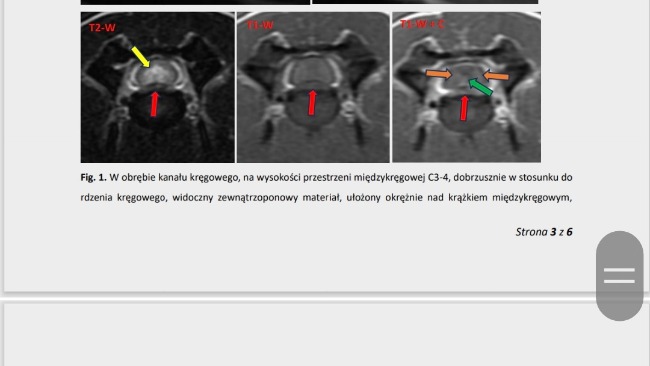

Nic nie wykryto. Zleciłam każde jedno możliwe badanie -w tym tomograf głowy. Okazało się,że jest coś na rdzeniu ( wszystko w opisie). Pies został wypisany ze szpitaliku,nie chodzi,przewraca się. Jedyne co może przywrócić jej sprawność to operacja,która kosztuje około 9 tysiecy( można zadzwonic do kliniki,zapytac). Przed tym jeszcze czeka nas konsultacja z neurochirurgiem.